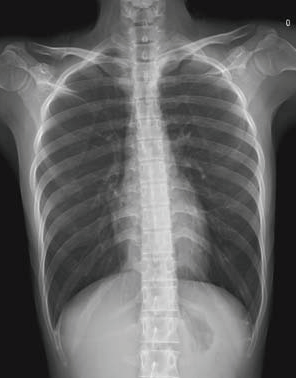

Lung imaging from a traditional X-ray machine

One of the most notable advantages is their ability to provide high-resolution images. They can detect very small anatomical details and abnormalities. For example, in lung cancer screening, CT scan machines can detect nodules as small as a few millimeters, which is unattainable with traditional X-ray machines. These high-resolution images allow doctors to clearly visualize the internal structures of organs, helping in making accurate diagnoses of a wide range of conditions.